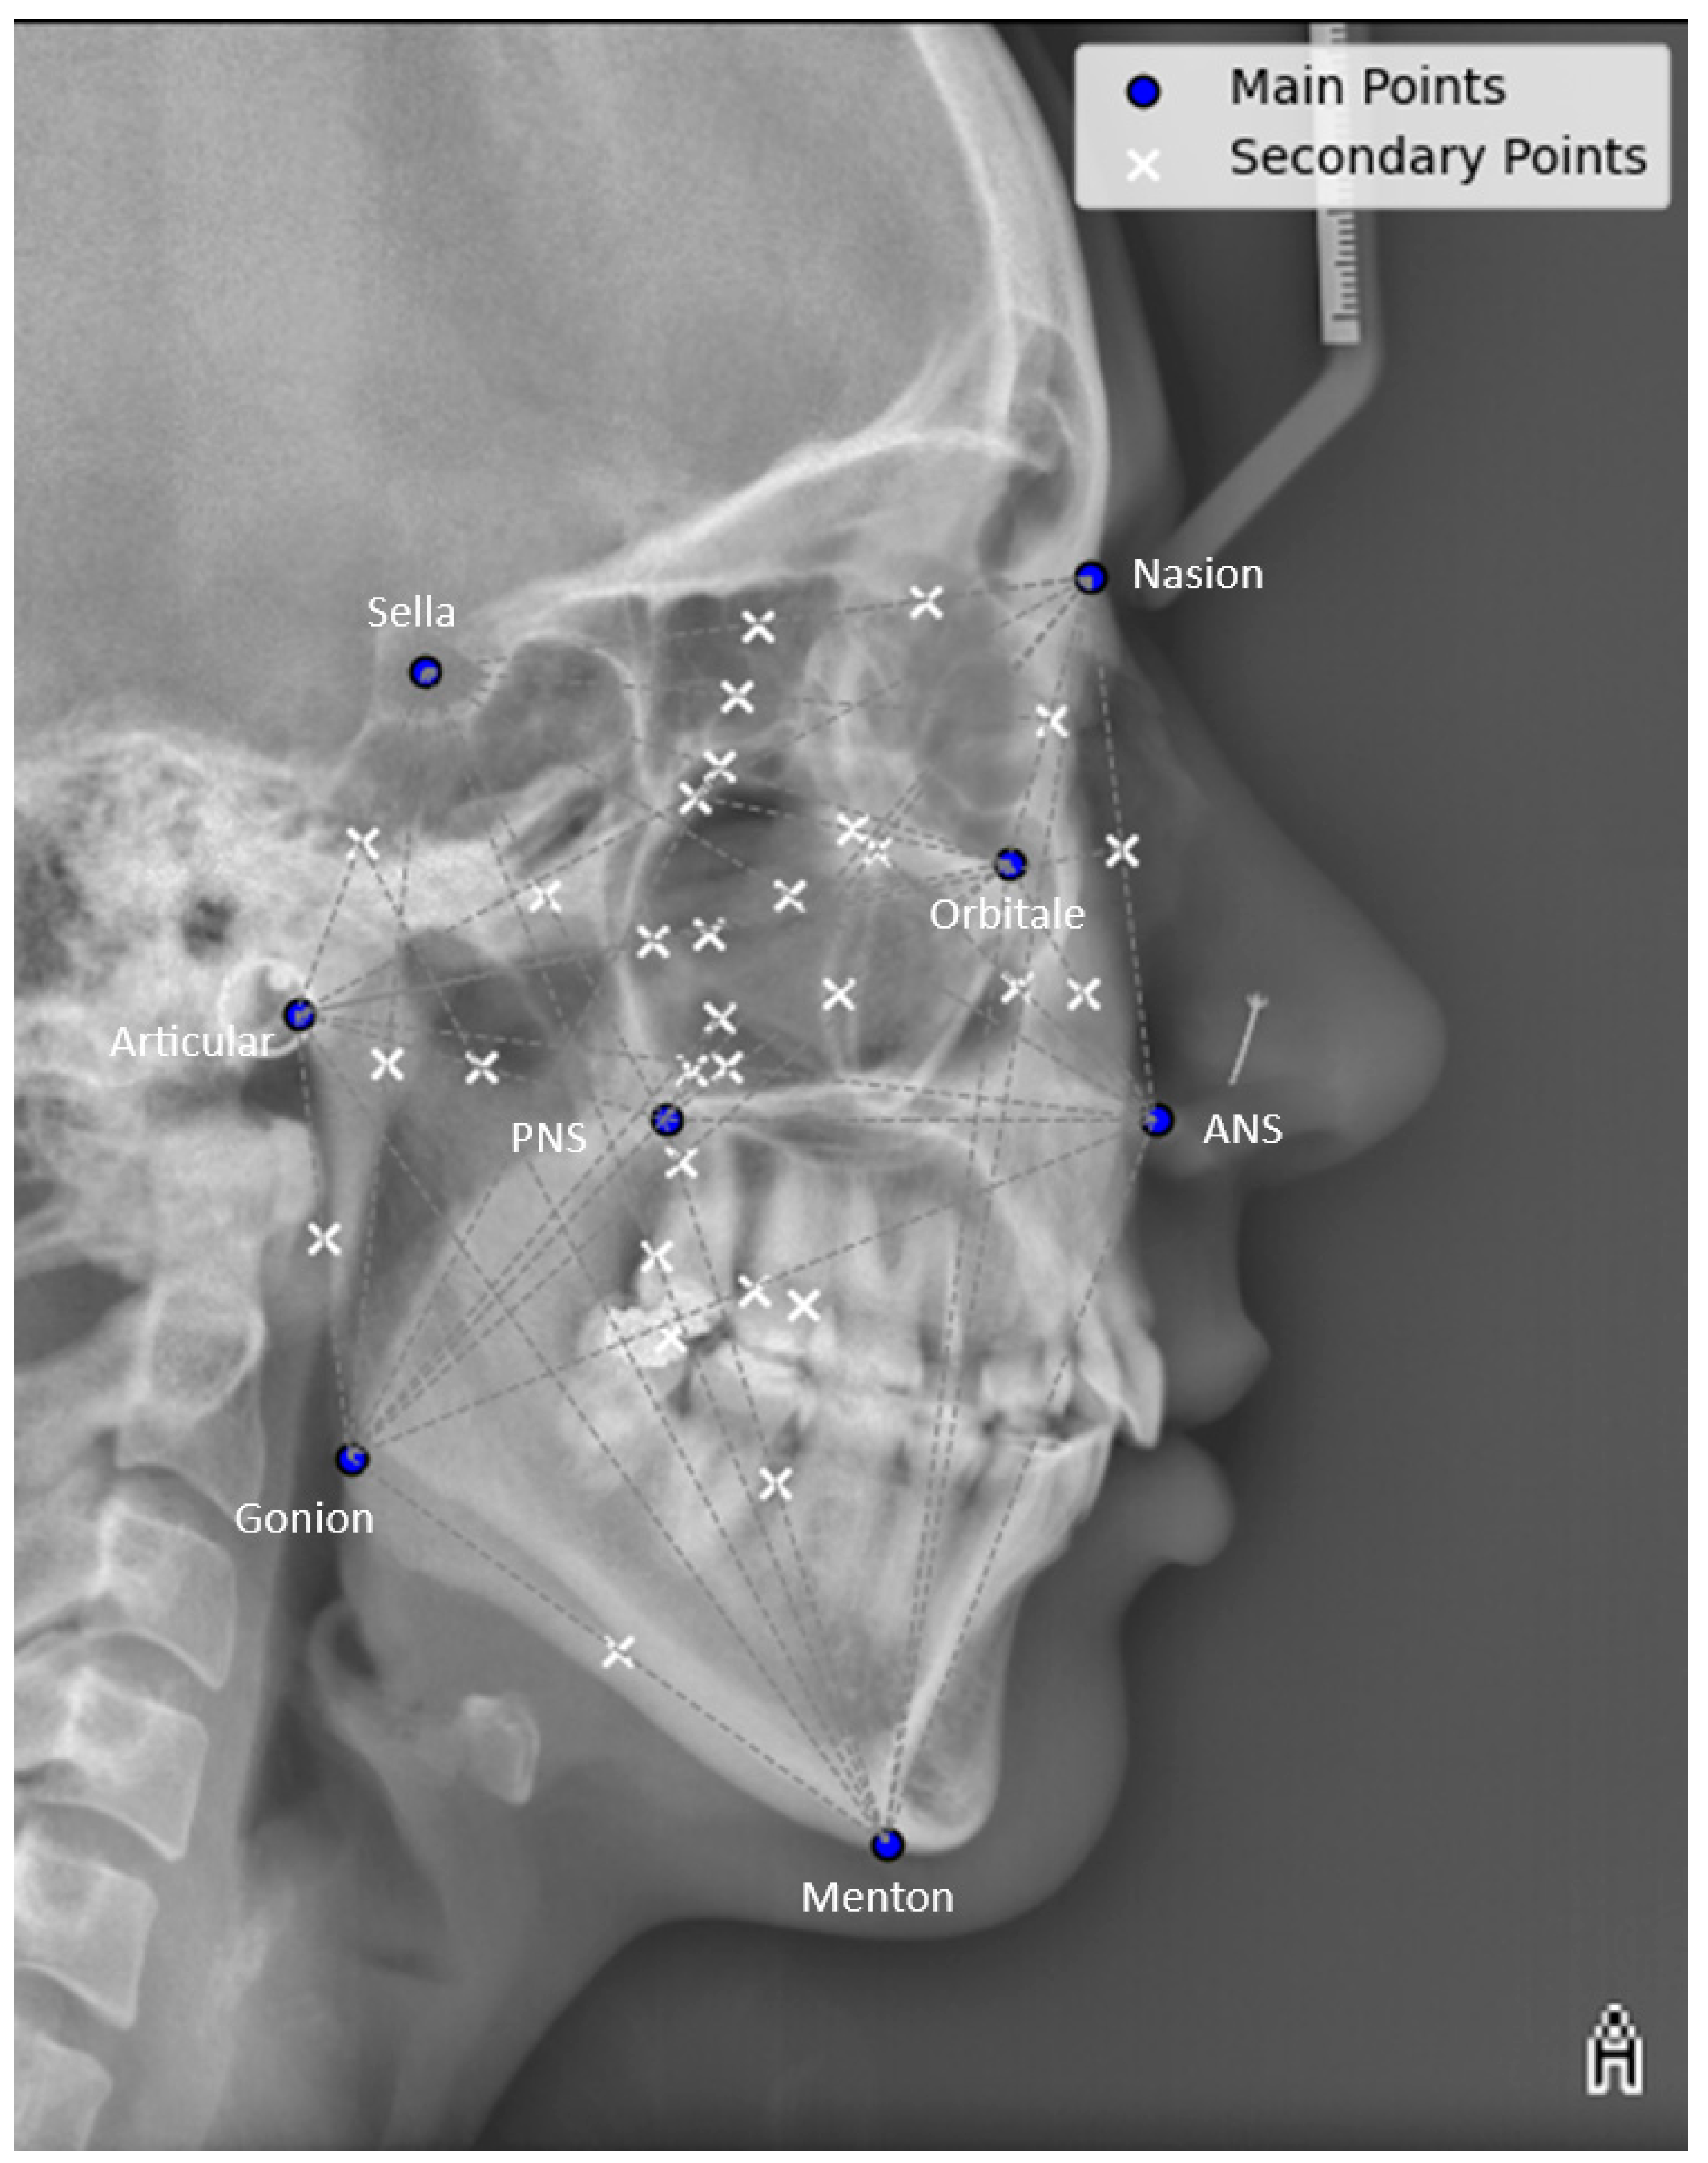

2.2. Radiographic Landmark Selection for Encoding Cranial AM Structural Patterns

| Landmark | Description |

|---|---|

| Nasion (NA) | The anterior point where the nasal and frontal bones intersect [42,43]. |

| Sella (S) | The midpoint of the pituitary fossa, also known as the sella turcica [42,43]. |

| Orbitale (Or) | The lowest point on the inferior margin of the orbit [42,43]. |

| ANS | Anterior nasal spine, the tip of the anterior nasal spine (sometimes modified as the point on the upper or lower contour of the spine where it is 3 mm thick) [42,43]. |

| PNS | The posterior nasal spine, defined as the tip of the palatine bone’s posterior spine at the junction between the hard and soft palates [42,43]. |

| Articulare (Ar) | The point where the contour of the posterior surface of the mandibular condyle intersects with the temporal bone [42,43]. |

| Gonion (Go) |

|

| Menton (Me) | The most inferior point on the chin [42,43]. |